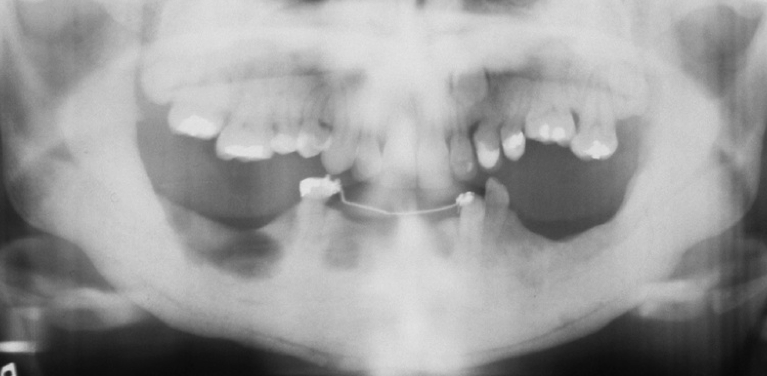

What is the likely Dx?

Cleidocranial dysplasia.

Key is the numerous unerupted permanent and supernumerary teeth.